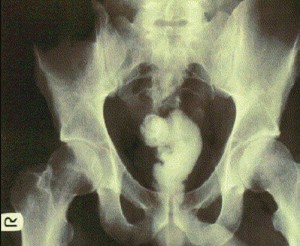

ნათურა

8 (1)